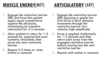

Muscle Energy Steps Review

MET vs ART review

GH Articulatory Tx: Spencer’s Technique

- Extension (every)

- Flexion (fine)

- Compression circumduction (cat)

- Traction circumduction (takes)

5a. Adduction and ER (an)

5b. Abduction (an) - IR (indoor)

- [Pump] traction with inferior glide (pee)